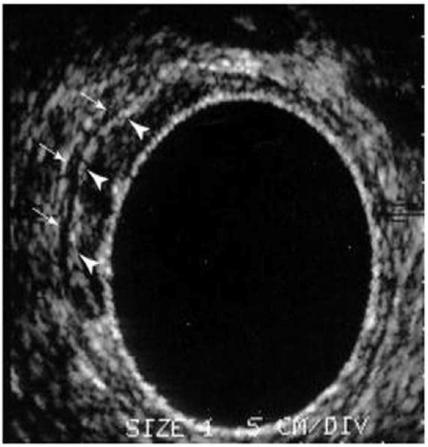

The success of pre-operative therapy over post-operative treatments means that a technique identifying prognostic factors pre-operatively is of potential benefit in modifying the intensity of pre-operative therapy according to risk of local or distant failure. Clinical trials incorporating robust and accurate assessment of prognostic factors and appropriate stratification of patients prior to therapy will enable objective comparison of treatment modalities and outcomes. Careful staging of rectal tumours results in selective pre-operative treatment strategies aimed at reducing local failure and distant failure in high risk patients.